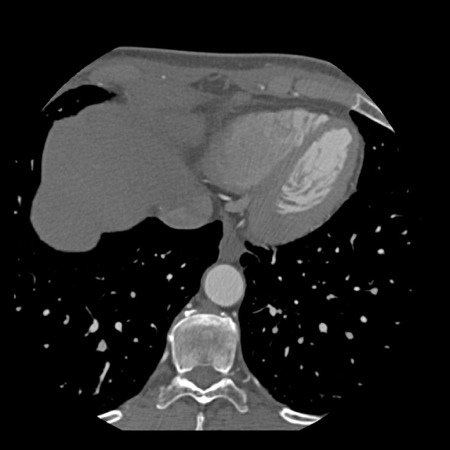

case 4 – CAD-RADS 3/P1/I+ thrombus left ventricle

First, scroll through the CTA images.

How would you describe the findings on the coronary CTA?

The findings are:

- Moderate (50-69%)

stenosis in the proximal LAD caused by a non-calcified plaque. - Variant of

sinoatrial (SA) nodal artery. The artery usually arises from the RCA as a second

branch after the conus artery, however in this case it arises from the LCX,

courses behind the aorta, anastomosing with the right atrium and with a small

branch supplies the SA-node of the heart. - Thrombus in the

apex of the left ventricle. - CTP was performed

in this patient. CTP showed a perfusion defect at stress imaging in the

territory of the LAD (I+), at rest no perfusion defect was visible.

This patient classifies as CAD-RADS 3/P1/I+, which means

this patient requires further investigation.